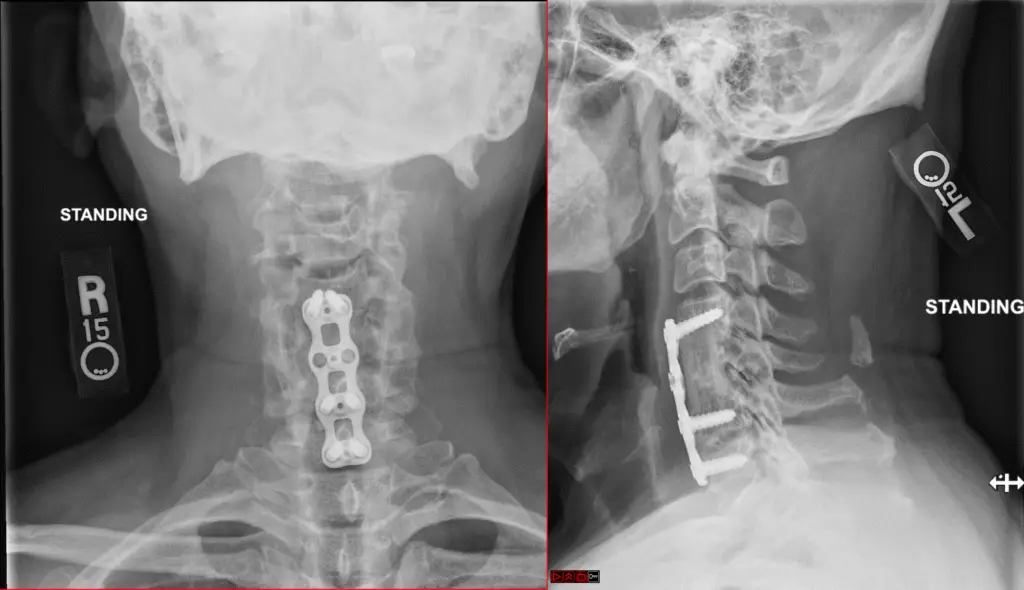

ACCF Postop 1024x503

Anterior Cervical Corpectomy and Fusion

anterior cervical c5 corpectomy and fusion